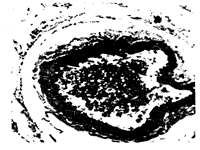

图4. 转基因鼠主动脉免疫组织化学染色照片

Figure 4.Photomicrograph of immunohistochemical

staining of aorta in transgen ic mice using

monoclonal antibody to human SR-A. ×400

对PCR阳性G1鼠的各种组织RNA进行RT-PCR,电泳结果显示(图3,Figure3),5只雄性首建鼠的G1鼠的主动脉、肾、肝等组织均有447bp特异性扩增带,而小肠、脑、心脏等组织RNA未检出特异性扩增带。提示,人SR-AI能在小鼠主动脉组织或血管丰富的组织中表达。小鼠组织切片免疫组织化学结果发现,主动脉内皮表面有棕褐色弧线形或月伢状颗粒,内皮细胞脱落处不着色,其它部位未见阳性颗粒(图4,Figure4)。肾内血管也见到同样的改变。提示人SR-AI基因表达有血管内皮细胞特异性。